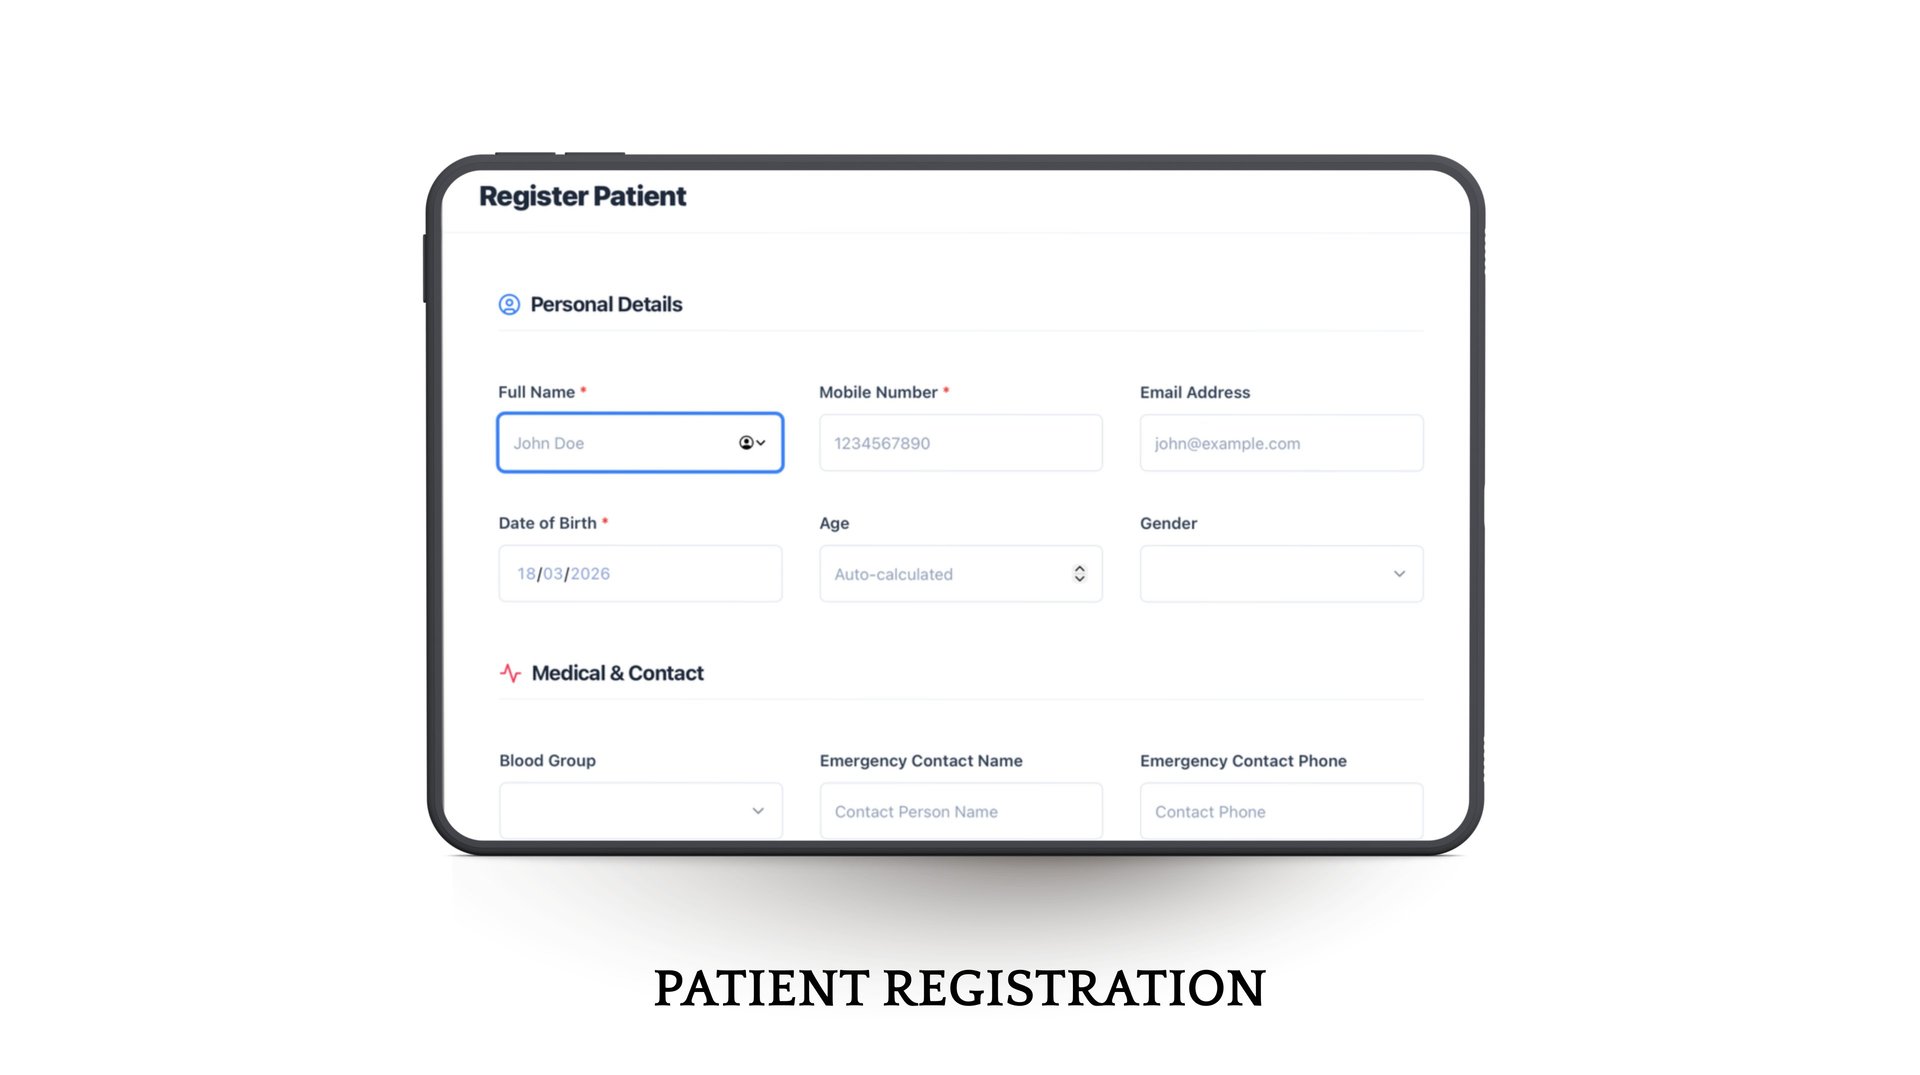

We empower Doctors, clinics and hospitals with our technology-enabled platform, enabling efficient and structured patient management through single account and health risk evaluations at the OPD level.

It simplifies everything—from patient entry to follow-up

Easy OPD workflows in few taps.